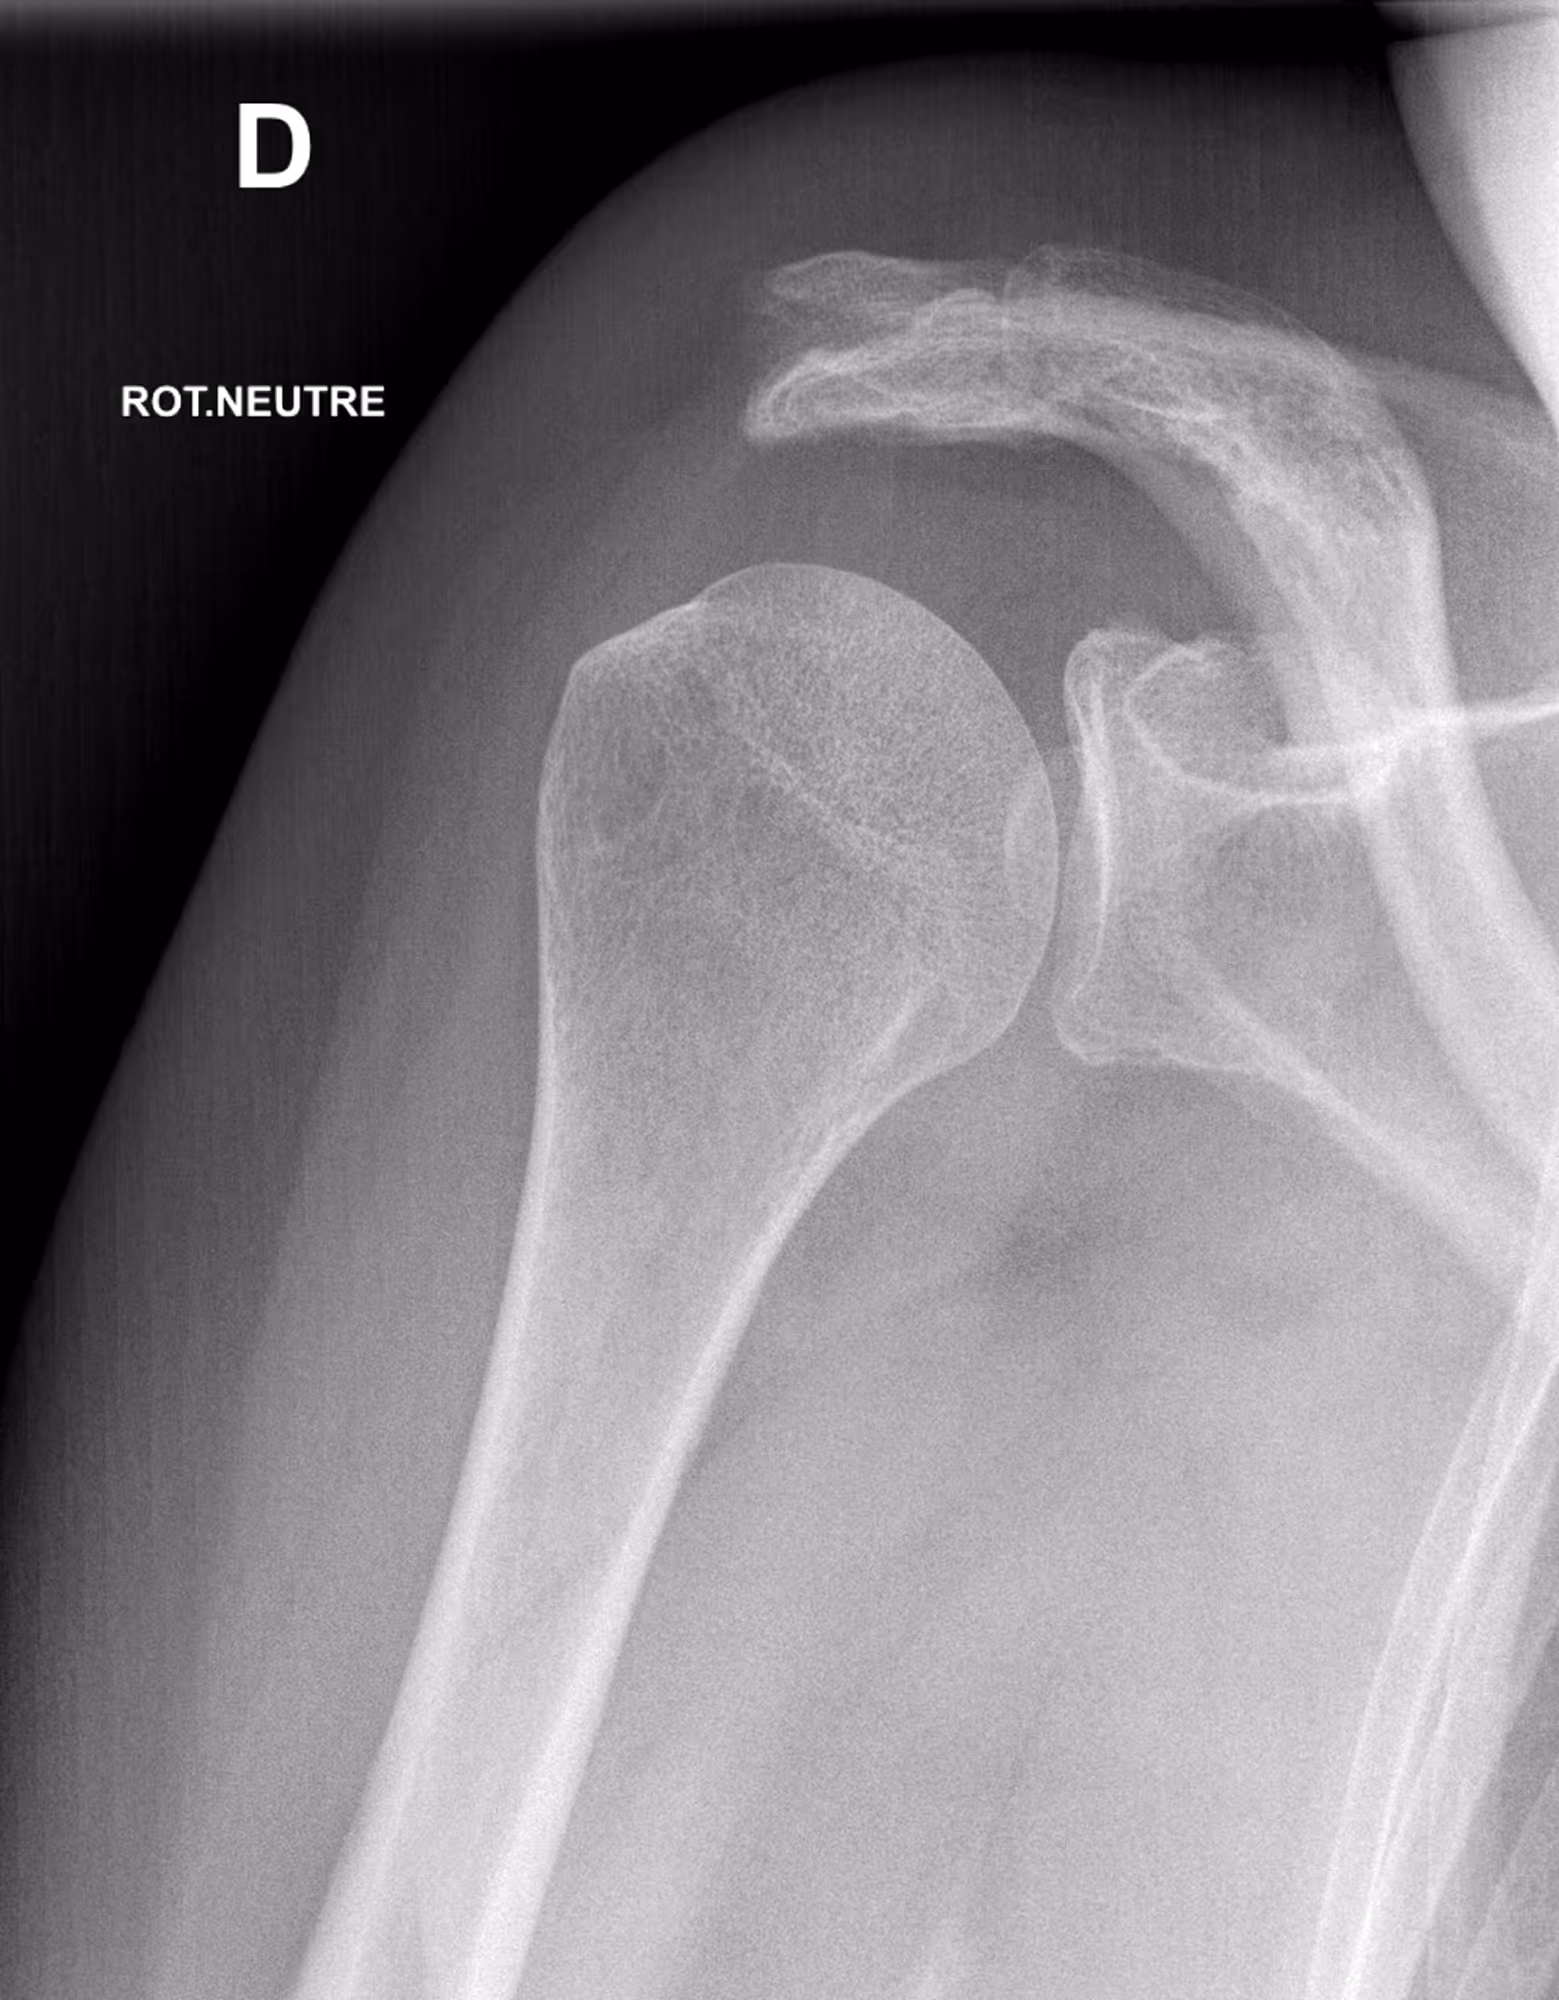

A 64-year-old female presenting with persistent left shoulder pain, undergoing evaluation prior to potential acromiosplasty.

Results

BoneMetrics found a critical shoulder angle within normal limits.

Frontal

Critical shoulder angle (CSA)